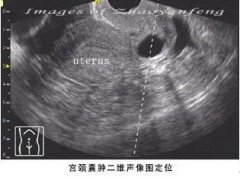

到底什么是宫颈囊肿? 引起宫颈囊肿的原因主要是由于慢性子宫颈炎引起的。由于子宫颈是阴道的鳞状上皮和子宫的单层柱状上皮交界的地方,因此,如果因为鳞状上皮增生,覆盖并阻